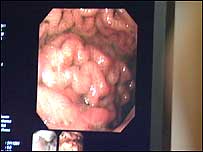

on drinking. Help at hand | | Counting

the cost - an unhealthy liver |